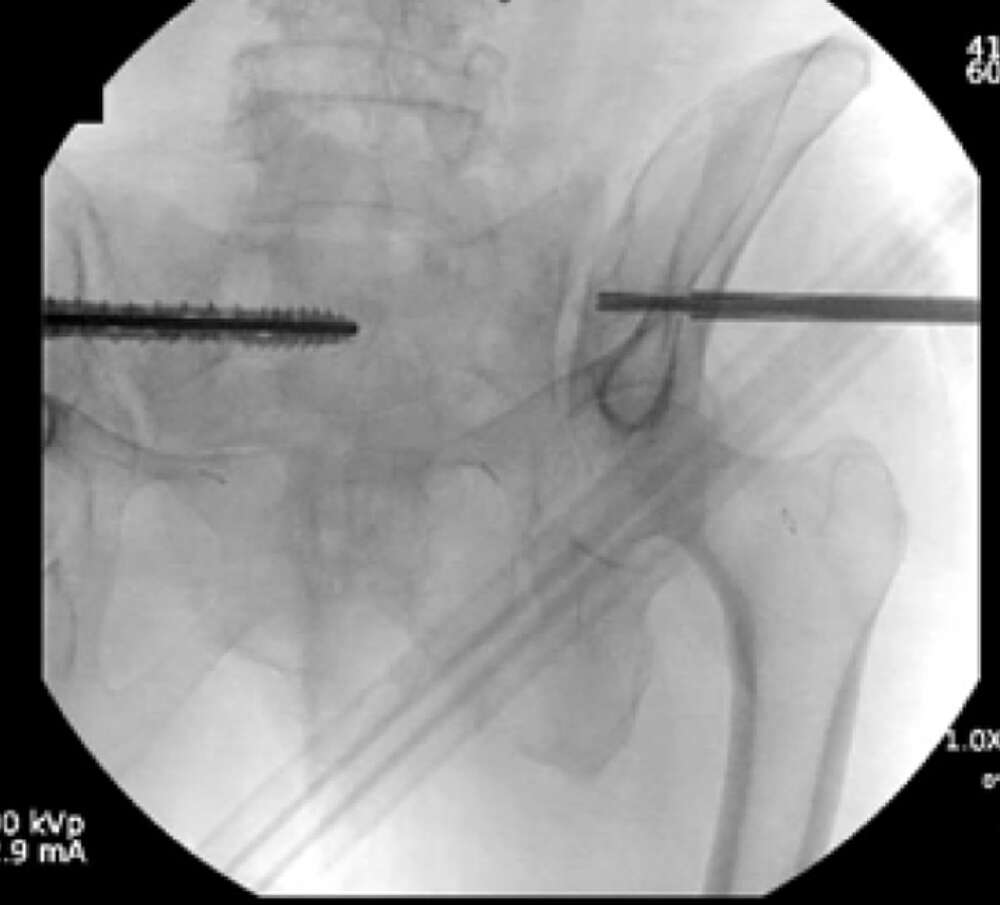

Surgical treatment:

• Bilateral sacral fracture fixation with iFuse TORQ®

Post-op:1,2

• Tolerated procedure well

• Immediate weight bearing as tolerated

• Ambulated 150 feet POD 1 and discharged home

• Pain improvement and healed fracture at 2 months

• No progression of kyphotic deformity